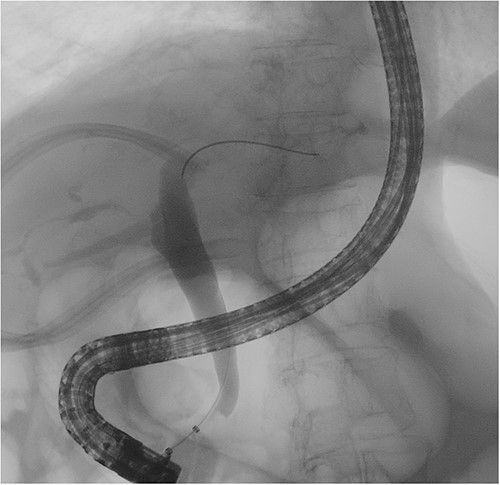

The subsequent endoscopic retrograde cholangiopancreatography showed no filling defect or luminal narrowing (Fig. 2). Pathological examination of the cyst wall revealed a benign cyst lined by cuboidal cells with acute chronic inflammation (Figs 4 and 5).

Cholangiography showed a smooth common bile duct wall without intraluminal filling defects.